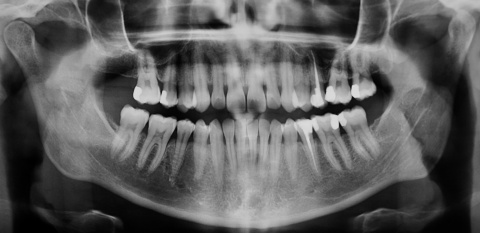

Eine 39-jährige Soldatin stellte sich im Januar 2020 mit Druckbeschwerden Regio 22 in unserer Abteilung vor. Wie auch in der vorangegangenen Falldarstellung konnten die Beschwerden mit Druck auf das Vestibulum verstärkt werden. Der Perkussionstest fiel deutlich positiv, der Vitalitätstest hingegen negativ aus. Eine erhöhte Lockerung des Zahnes lag, trotz des eindrucksvollen Röntgenbefundes, nicht vor. Erste Beschwerden traten laut Aussage der Patientin bereits 2014 auf. Das zu diesem Zeitpunkt angefertigte Röntgenbild zeigte keinen signifikanten pathologischen Befund, woraufhin die Situation weiterhin beobachtet wurde. Das aktuell angefertigte Röntgenbild zeigte eine umfangreiche periapikale Osteolyse, welche sich bis zu den Wurzelspitzen 21 und 23 erstreckte. Der Vitalitätstest der beiden benachbarten Zähne fiel positiv aus.

Nach Wurzelfüllung des Zahnes 22, erfolgte die intrasulkuläre Schnittführung mit Entlastungenschnitten mesial der Zähne 21 und 24, um einen ausreichenden Abstand der Schnittränder zum Defekt zu gewährleisten. Bereits während der Lappenbildung imponierte ein umfangreicher Defekt des vestibulären Knochens in Höhe der Wurzelspitze des Zahnes 22. Die Osteolyse dehnte sich bis zu den Wurzeln der Zähne 21 und 23 aus und durchbrach zudem die palatinale und nasale knöcherne Begrenzung. Nach Entfernung des Granulationsgewebes deckten wir den Defekt mit einer resorbierbaren Kollagenmembran (Creos Xenoprotect der Firma Nobel Biocare AB, Göteborg) ab und vernähten den Mukoperiostlappen spannungsfrei.

Der chirurgische Eingriff erfolgte ohne Entfernung der Wurzelspitze des Zahnes 22. Laut der bereits erwähnten Untersuchung von Song et al.[5] lag unter anderem eine Ursache für den Misserfolg einer durchgeführten Wurzelkanalbehandlung zu 8,7 % in einer komplexen anatomischen Struktur und zu 19,7 % in einem übersehenen Wurzelkanal. Das mechanische und chemische Aufbereiten des hier vorgefundenen Wurzelkanals sowie die Obturation waren jedoch auch ohne Resektion der Wurzelspitze problemlos möglich. Wie in Abbildung 11 zu sehen, kam es zu einer intendierten Überfüllung des Wurzelkanals. Daher ist von einer Nischenbildung im apikalen Bereich nicht auszugehen. Das überpresste Wurzelfüllmaterial konnte im Rahmen des anschließenden chirurgischen Eingriffs zuverlässig entfernt werden. Eine zusätzliche Wurzelspitzenresektion hätte in diesem Fall keinen entscheidenden Vorteil gebracht. Kritisch hingegen ist zu betrachten, ob wir der kombiniert endodontisch-chirurgischen Therapie nicht gleich zu Anfang der Behandlungsplanung den Vorzug hätten geben sollen.

Zum Einfluss der Größe apikaler Läsionen auf die Erfolgsraten gibt es auf der einen Seite Studien, die geringere Erfolgsraten bei zunehmender Größe der Läsion zeigen [15]. Andererseits postulieren andere Untersuchungen keinen signifikanten Einfluss der Läsionsgröße auf den Behandlungserfolg [16]. Ausschlaggebend in dieser Kasuistik war, dass die sich die Läsion vermutlich über einen sehr langen Zeitraum (erstes Auftreten der Beschwerden im Jahre 2014) entwickelt hat, was sich wahrscheinlich in der Quantität und Qualität der vorhandenen Mikroorganismen niedergeschlagen haben dürfte. Zum anderen gab das Wiederauftreten der Beschwerden und die neu entstandene Fistelung Grund zur Annahme, dass auch extraradikuläre Bakterien die Entzündungsreaktion fördern. Ein im Jahre 2006 von Nair [17] durchgeführtes Review führt mögliche Keime in periradikulären Läsionen (z. B. Aktinomyzeten) als Ursache für persistierende Infektionen auf. Unterstützt wird das von uns gewählte Vorgehen durch die Studienergebnisse von Ng et al. [18], die eine reduzierte Erfolgswahrscheinlichkeit von nicht-chirurgischen Wurzelkanalbehandlung bei Vorliegen einer periapikalen Osteolyse zeigten. Gleichzeitig reduzierte sich die Prognose mit Zunahme der Läsionsgröße.